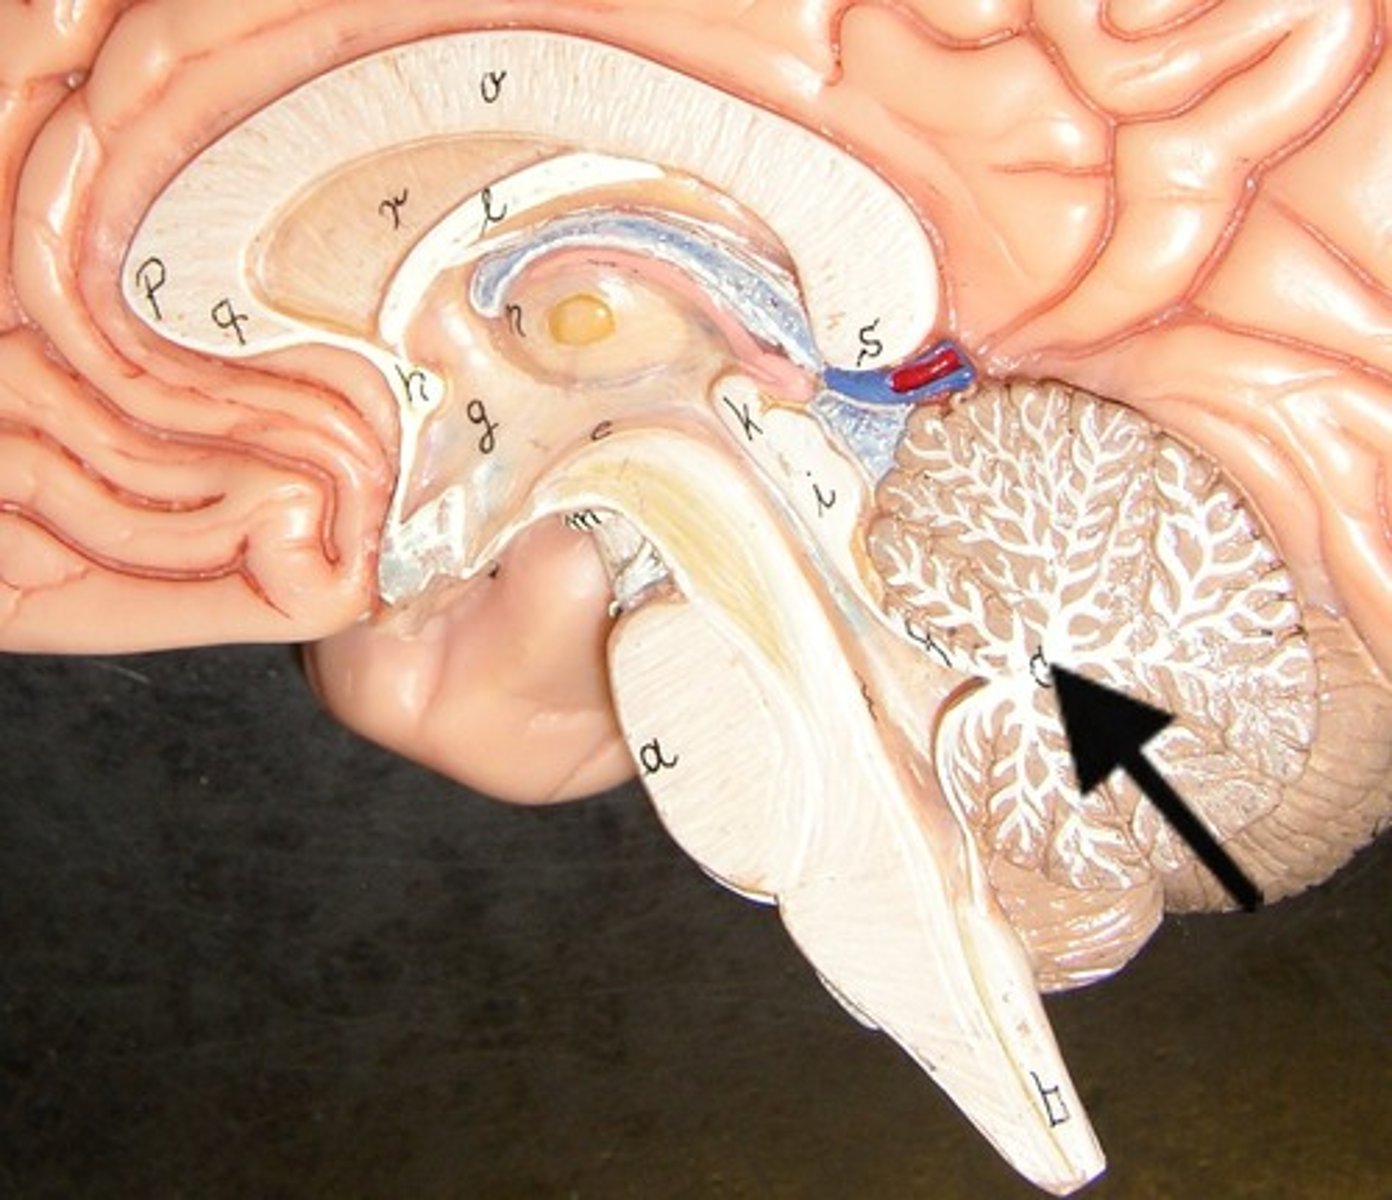

cerebellum

the "little brain" at the rear of the brain; functions include processing sensory input and coordinating movement output and balance

arbor vitae

corpus callosum

A thick band of axons that connects the two cerebral hemispheres and acts as a communication link between them.

midbrain (mesencephalon)

pons

medulla oblongata

Diencephalon

central part of the brain made up of the thalamus, hypothalamus, and epithalamus

thalamus

hypothalamus

pituitary gland